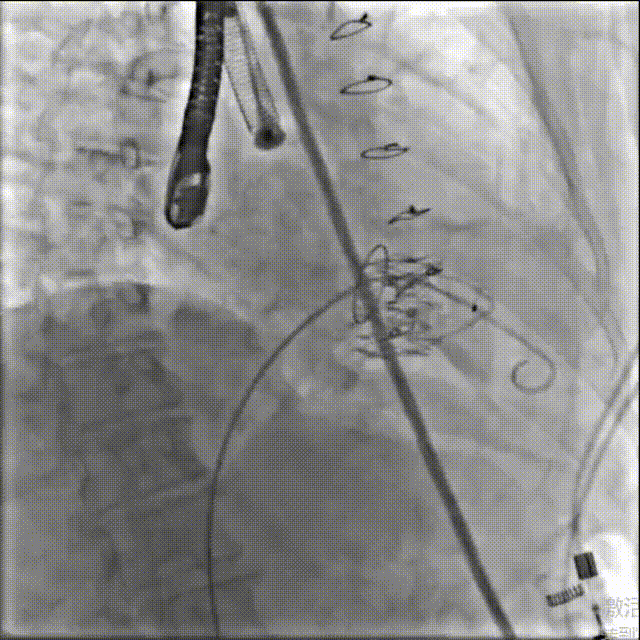

手术在患者全麻状态下进行,采用经右侧颈静脉作为入路,将装载有人工瓣膜的输送器缓慢推送至右心房;并在经食道超声和DSA的引导下小心调整输送器角度,将输送器送入右心室;逐步释放瓣膜锚定装置和盘片,调整瓣膜位置后,锚定瓣膜完成植入。术后右房压明显下降,从术前的25/10(16) mmHg降至术后即刻的12/7(10) mmHg,术后超声提示人工三尖瓣同轴性良好,固定牢固,无反流及瓣周漏手术室即刻拔除气管插管。

术后造影